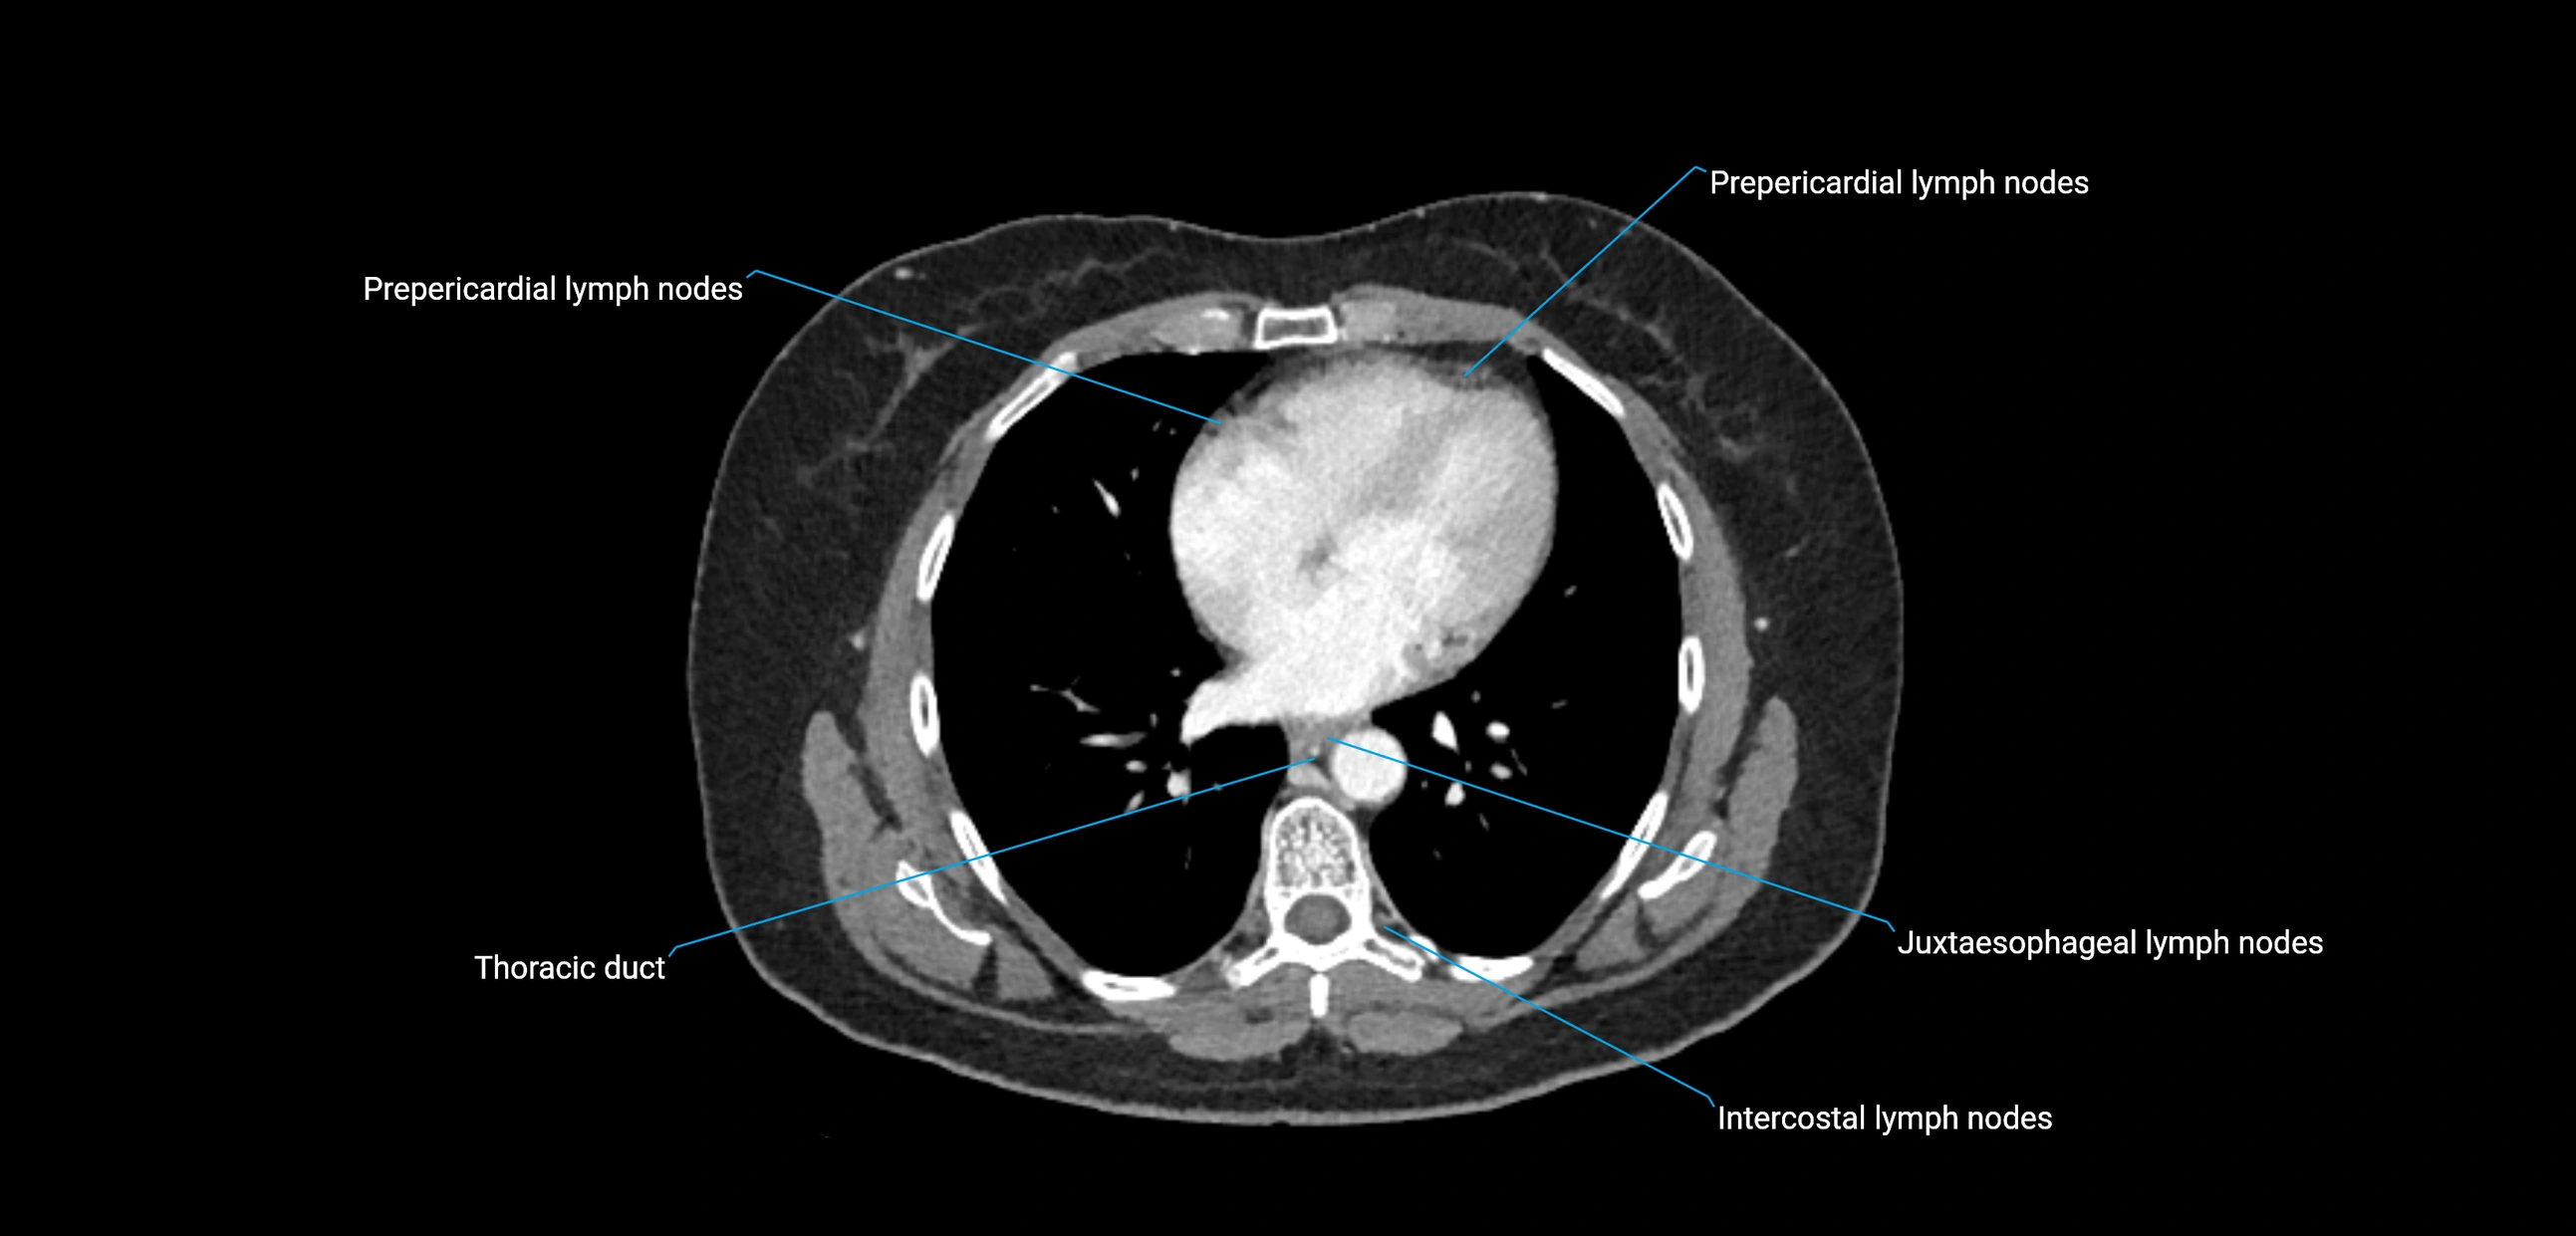

MRI images

image